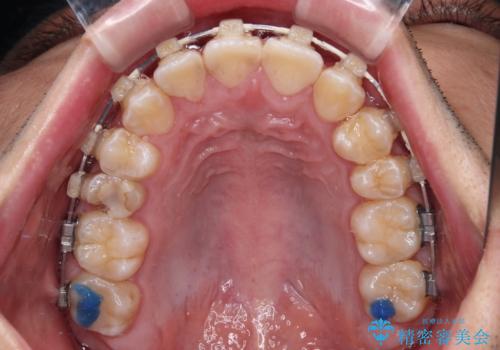

- 矯正装置

- 審美装置

- 2年5ヶ月

- デコボコと奥歯の咬み合わせのズレを気にして来院された患者様です。

骨格的に、下顎が右側にずれており、左側の咬み合わせに鋏状咬合などのアンバランスが生じている状態でした。

また、上顎前歯に欠損が1本あり、上下ともに前歯部に叢生が認められ、下顎前歯の大半が隠れてしまうほどの過蓋咬合も認められました。

咬合平面を平坦にしながら前歯の咬み合わせを挙上し、デコボコと鋏状咬合も改善していくこととしました。